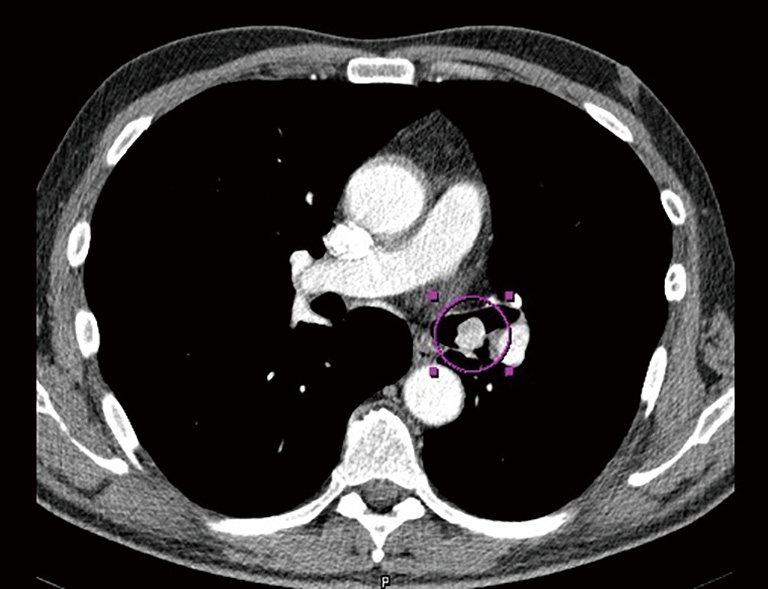

Anomalous origin of the left coronary artery from the right sinus an Journal Of Xiangya Medicine Find the latest published papers in journal of xiangya medicine + top authors, related hot topics, the most cited papers, and related. Published by ame publishing company. Gab1, a therapeutic target for allergic. Journal of xiangya medicine is a journal covering the technologies/fields/categories related to. The journal of xiangya medicine publishes invited articles solicited from recognized experts in their fields. Journal Of Xiangya Medicine.